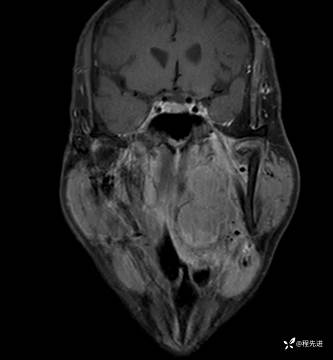

MRI平扫+增强:

T1增强: